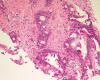

Pulmonary enteric adenocarcinoma (PEAC) is an extremely rare type of non-small cell lung cancer (NSCLC) with a histologic pattern that mimics metastatic colorectal cancer (MCC). The main clinical symptoms in PEAC patients are dyspnoea, coughing, hemoptysis, and chest and back pain. The first article about PEAC appeared in 1991 in the form of a case report. As a variant of invasive lung carcinoma, only a small number of case reports and clinical research studies have been carried out, and the only one guidance on diagnosis and treatment is the WHO Tumor Classification book. It is important for doctors to distinguish PEAC from MCC to extend survival time and improve the quality of life. We reviewed the existing literature regarding the diagnosis, treatment, and prognosis of PEAC to provide some valuable clinical references.